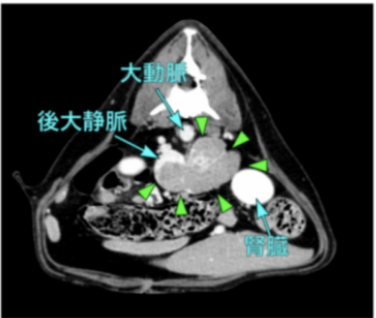

超音波検査、CT検査より、左副腎腫瘍、後大静脈浸潤(腫瘍栓)が認められた

CT画像、カテコラミン分画より褐色細胞腫を疑い、外科的切除を行った。